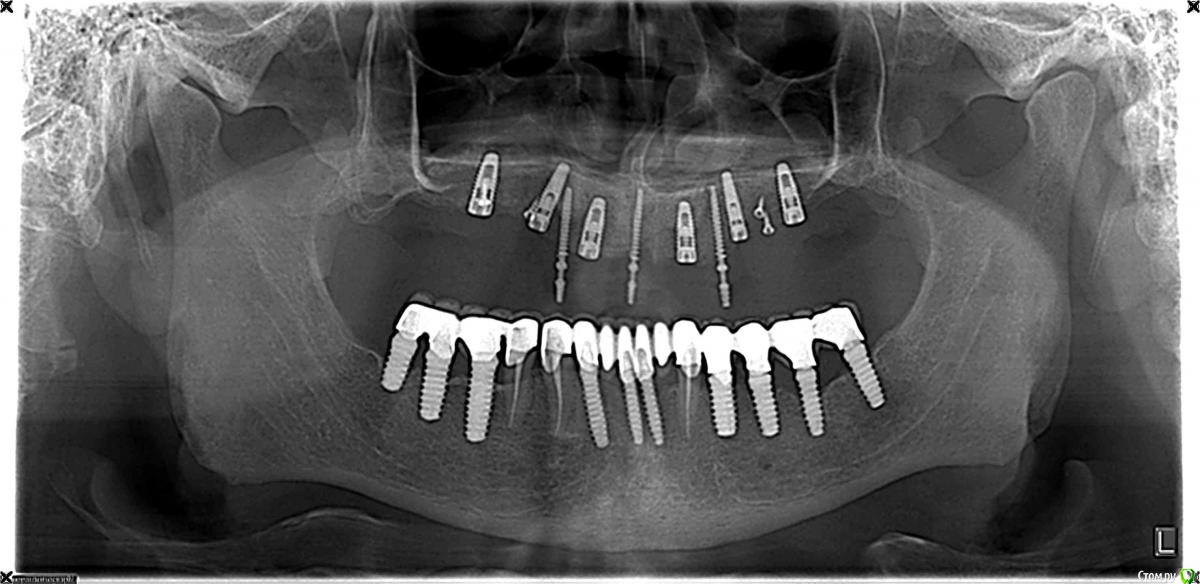

SergeyAL Опубликовано 11 сентября, 2015 Автор Поделиться Опубликовано 11 сентября, 2015 на первом этапе была проведена костная пластика по Кури в 1 и 2 квадрантах + двухсторонний синуслифт, доступ вертикальный тоннель. врменная реставрация на остатках зубов во фронтальном отделе.через 5 месяцев зубы подвели, пришлось проводить удаление зубов, одномоментную имплантацию, установку временных имплантатов во фронтальнос участке и фиксировать временную конструкцию на временных имплантатах.через 4 месяцараскрытие имплантатов с пластикой кератинизированной десны СДТвременное протезирование на постоянных имплантатахчерез 3 месяца постоянное протезирование на имплантатах последний снимок через 8 месяцев после постоянного протезирования. 4 Ссылка на комментарий